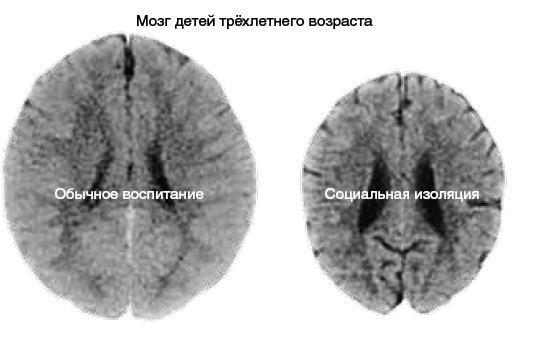

Поэтому, чтобы не быть голословным, я просто предъявлю вам иллюстрацию из знаменитого исследования, проведённого американским психиатром, старшим научным сотрудником Академии детских травм в Хьюстоне (Техас) Брюсом Перри (рис. 42)64.

Рис. 42.  Компьютерная томография мозга двух трёхлетних детей: слева мозг ребёнка, который воспитывался в обычной социальной среде, справа — ребёнка, который имел минимальное количество социальных контактов.

Слева на изображении вы видите мозг обычного ребёнка трёх лет, справа — «здорового», в сущности, ребёнка, с одним лишь отличием — он был практически полностью лишён социальных контактов и родительской опеки.

Этот мозг не только сильно меньше в размерах, что само по себе катастрофа, но плюс к этому отмечаются расширенные желудочки мозга и отчётливо видны признаки атрофии коры головного мозга.